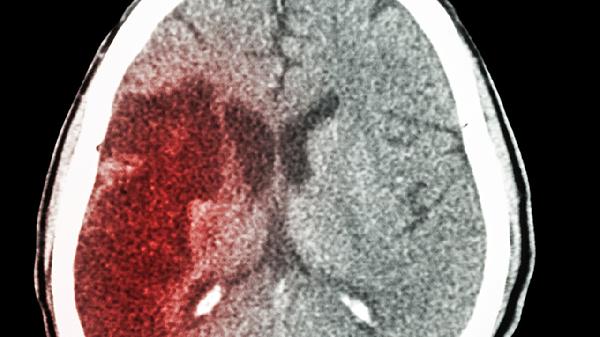

孕妇禁用脑得生丸,因含活血化瘀成分可能引起子宫收缩。出血性疾病患者如消化道出血、脑出血急性期禁用,可能加重出血风险。哺乳期妇女慎用,药物成分可能通过乳汁影响婴儿。对该药任何成分过敏者禁止使用,过敏体质者需提前告知医生。